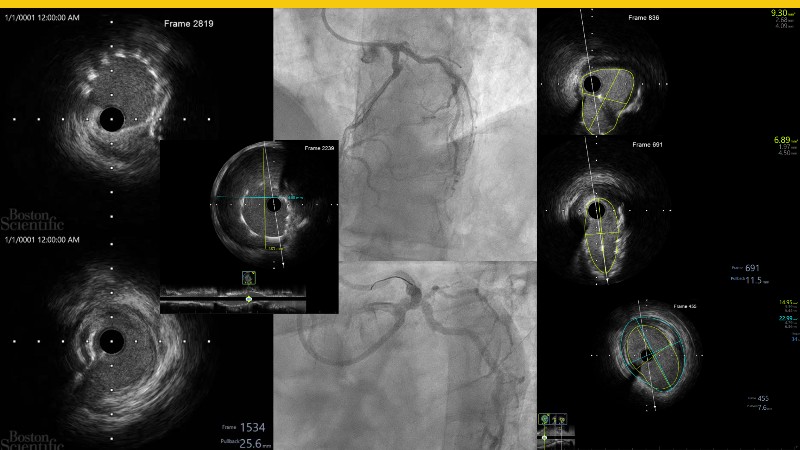

Discover how the next-generation RevoEdge high-pressure cutting balloon is transforming PCI with innovative design and proven clinical outcomes. This session presents a multicenter randomised trial and real-world case discussions, showcasing RevoEdge’s effectiveness in tackling resistant, complex lesions—including long, tortuous, and fibrotic cases. Learn practical tips, tricks, and intravascular imaging insights to optimize lesion preparation and improve patient outcomes. Don’t miss this opportunity to see how RevoEdge helps you cut through challenges and conquer PCI complexities.

- To explore the innovative design of RevoEdge: the next-generation high pressure cutting balloon

- To learn about the clinical benefits and tips and tricks of using RevoEdge high pressure cutting balloon in different types of complex lesions through case-based discussion